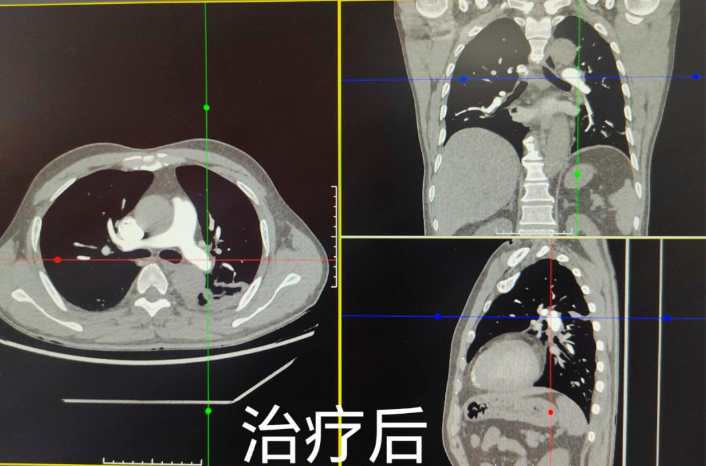

术中DSA造影见左肺动脉主干及分支及右肺下叶肺动脉内见充盈缺损影,其相应肺野血供较差,符合肺动脉栓塞症诊断。术中通过导管快速注入尿激酶对肺动脉主干及其分支内的血栓实施有效接触溶栓。术后继续给予抗感染、抗凝及溶栓治疗,手术联合药物治疗非常成功,经评估,符合下腔静脉滤器取出指征,将滤器取出。现患者已康复出院,对我院急危重症救治能力给予了高度评价,这项新技术的成功开展,标志着我院在血管介入治疗方面又上一新台阶。